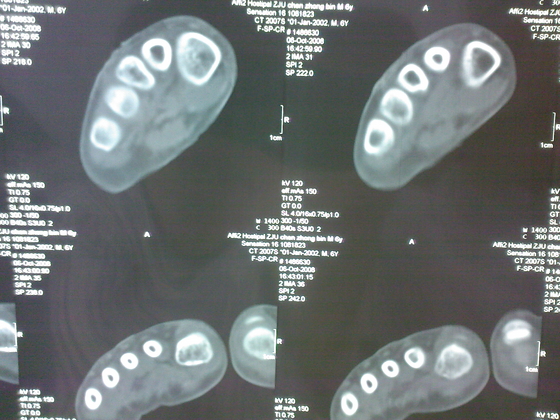

把病理送浙一医会诊后诊断为:骨外软骨瘤。同时做了CT检查。暂未予治疗。

今天把创面情况跟CT发上请大家看看。

继续发CT片

继续还有几张。